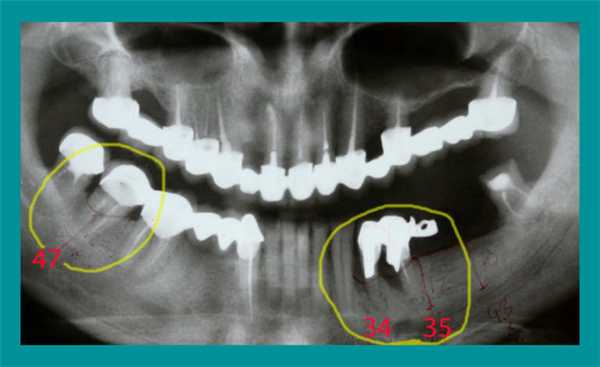

Согласно данным ортопантомограммы было определено: деструкция и резорбция, т.е. потеря и убыль костной ткани в области корней зубов под металлокерамическими коронками на нижней челюсти слева и под мостовидным протезом в области верхушки корней справа. Перелечиванию и использованию в ортопедической конструкции эти зубы не подлежали, поэтому было показано их удаление.

Справа был установлен один имплантат. Из-за большой протяженности зубного дефекта на левой стороне нижней челюсти установили три имплантата - оптимальное количество для поддержки мостовидного протеза из четырех металлокерамических коронок. На панорамном снимке видно расположение установленных имплантатов.